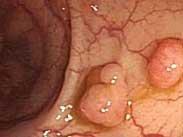

多發性消化道息肉綜合征

• 多發性消化道息肉綜合征

628健康網為您分享有關多發性消化道息肉綜合征的癥狀,多發性消化道息肉綜合征的治療方法,多發性消化道息肉綜合征的預防...